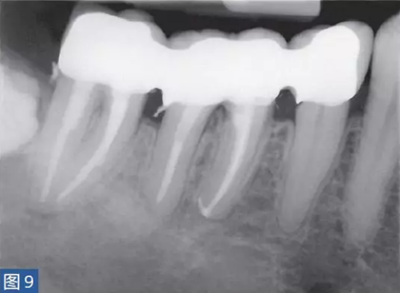

急性根尖膿腫(圖8 和9)是一種局部的或者彌漫性的液性病變。由壞死牙髓產(chǎn)生的微生物和非微生物刺激所引起的嚴重炎癥反應(yīng)造成了根尖周組織的破壞。患者通常表現(xiàn)出中度至重度疼痛,根據(jù)嚴重程度還可能出現(xiàn)發(fā)熱和白細胞增多的全身癥狀。

臨床診斷顯示牙髓電活力測試結(jié)果陰性。叩診和觸診通常會引起疼痛。如果膿腫僅限于骨內(nèi),則不出現(xiàn)腫脹癥狀。放射學檢查,根尖周組織表現(xiàn)從無變化到發(fā)生明顯變化。

圖8:47 牙齒AAA。術(shù)前X 線片?;颊呔驮\時有發(fā)燒癥狀,且叩診和觸診疼痛明顯。

圖9:47 牙齒AAA。根管治療后?;颊咴谄浼彝パ泪t(yī)處做臨時義齒修復(fù)12 個月后的檢查。